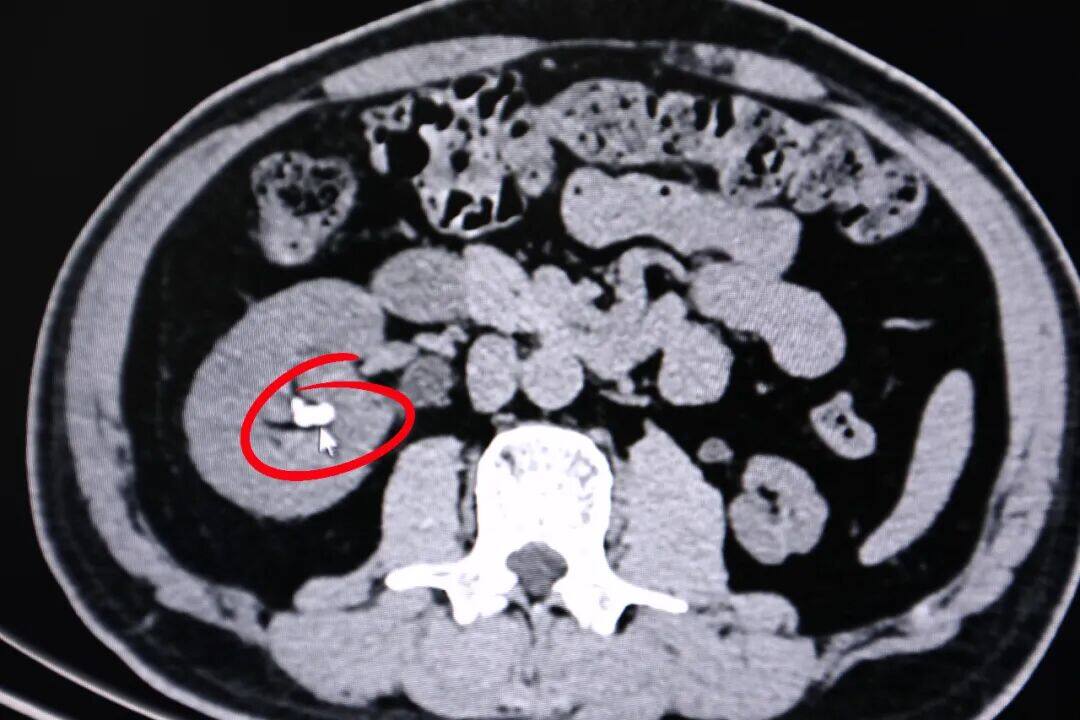

▲患者肾结石影像

明确病因后,医院泌尿外科团队制定个性化精准治疗方案,为患者实施手术,行膀胱颈口部分电切。术中,考虑患者右侧为完全重复肾畸形,团队使用前列腺电切镜于膀胱颈口黏膜隆起处进行电切,暴露出隐藏的输尿管,在输尿管镜下应用钬激光碎石,解除输尿管梗阻后,将结石精准粉碎并取出。术后患者恢复良好,顺利康复。